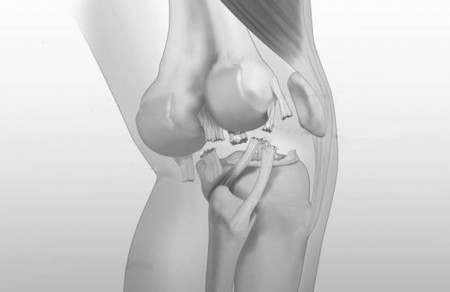

Complexe knie instabiliteiten worden veroorzaakt door trauma’s waarbij twee, drie of alle vier de ligamenten (banden) in de knie tegelijkertijd scheuren, soms in combinatie met vaat- en of zenuwletsel. Als twee of drie of zelfs alle vier van de ligamenten worden beschadigd, wordt de blessure zeer veel moeilijker te behandelen. Dit complexe knieletsel wordt een multiligamentair knieletsel of knie luxatie genoemd.